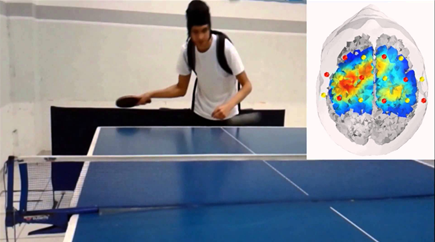

图像:乒乓球实验期间的fNIRS [15]

当任务开始时,会消耗氧气,随着复杂性的增加,对氧气的需求也会增加。功能磁共振成像测量消耗了多少氧气。fNIRS还可以测量该区域有多少氧气含量。

但是,fNIRS的时间分辨率不如EEG。fNIRS每秒采集10个样本,而EEG每秒500到1000个样本。而且空间分辨率不如fMRI。例如,fMRI可以对大脑皮层下的大脑区域成像,而fNIRS无法分析经过皮质的图像,无法捕获任何皮质下激活。事实上,许多研究人员在SfN展示了他们使用该仪器作为其EEG或fMRI数据的补充。[16]